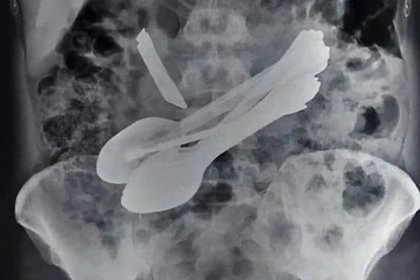

Ocho cucharas de distintos tamaños, dos cepillos de dientes, un cuchillo de cocina y dos destornilladores.

Todo eso tuvieron que sacar los doctores del estómago de un adulto hindú que padece un grave trastorno psicológico.

El hombre de 35 años de edad, identificado como Karan Sen, llegó al hospital Lal Bahadur Shastri, quejándose de un dolor horrible. En ese instante los doctores le hicieron una radiografía y encontraron una punta afilada, sin embargo, jamás pensaron que eso solo sería la punta del iceberg. Uno de los doctores descubrió que aquella punta de cuchillo le estaba perforando el estómago, y en ese instante se tomó la decisión de operarlo de emergencia.

La cirugía duró más de tres horas, ya que después del cuchillo fueron saliendo más objetos metálicos. “Primero observamos una punta sobresaliendo en su estómago. En ese instante lo operamos sin perder tiempo, pero durante la cirugía descubrimos más objetos adentro de su cuerpo. Había un cuchillo, ocho cucharas, dos destornilladores y dos cepillos de dientes”, comentó el Dr. Rajneesh Pathania, de la Facultad de Medicina Lal Bhadur Shastri.